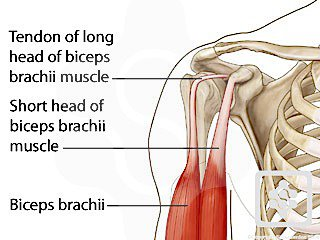

What is the superior tendon (highest point) shown here?

Tendon of the long head of the biceps brachii muscle.